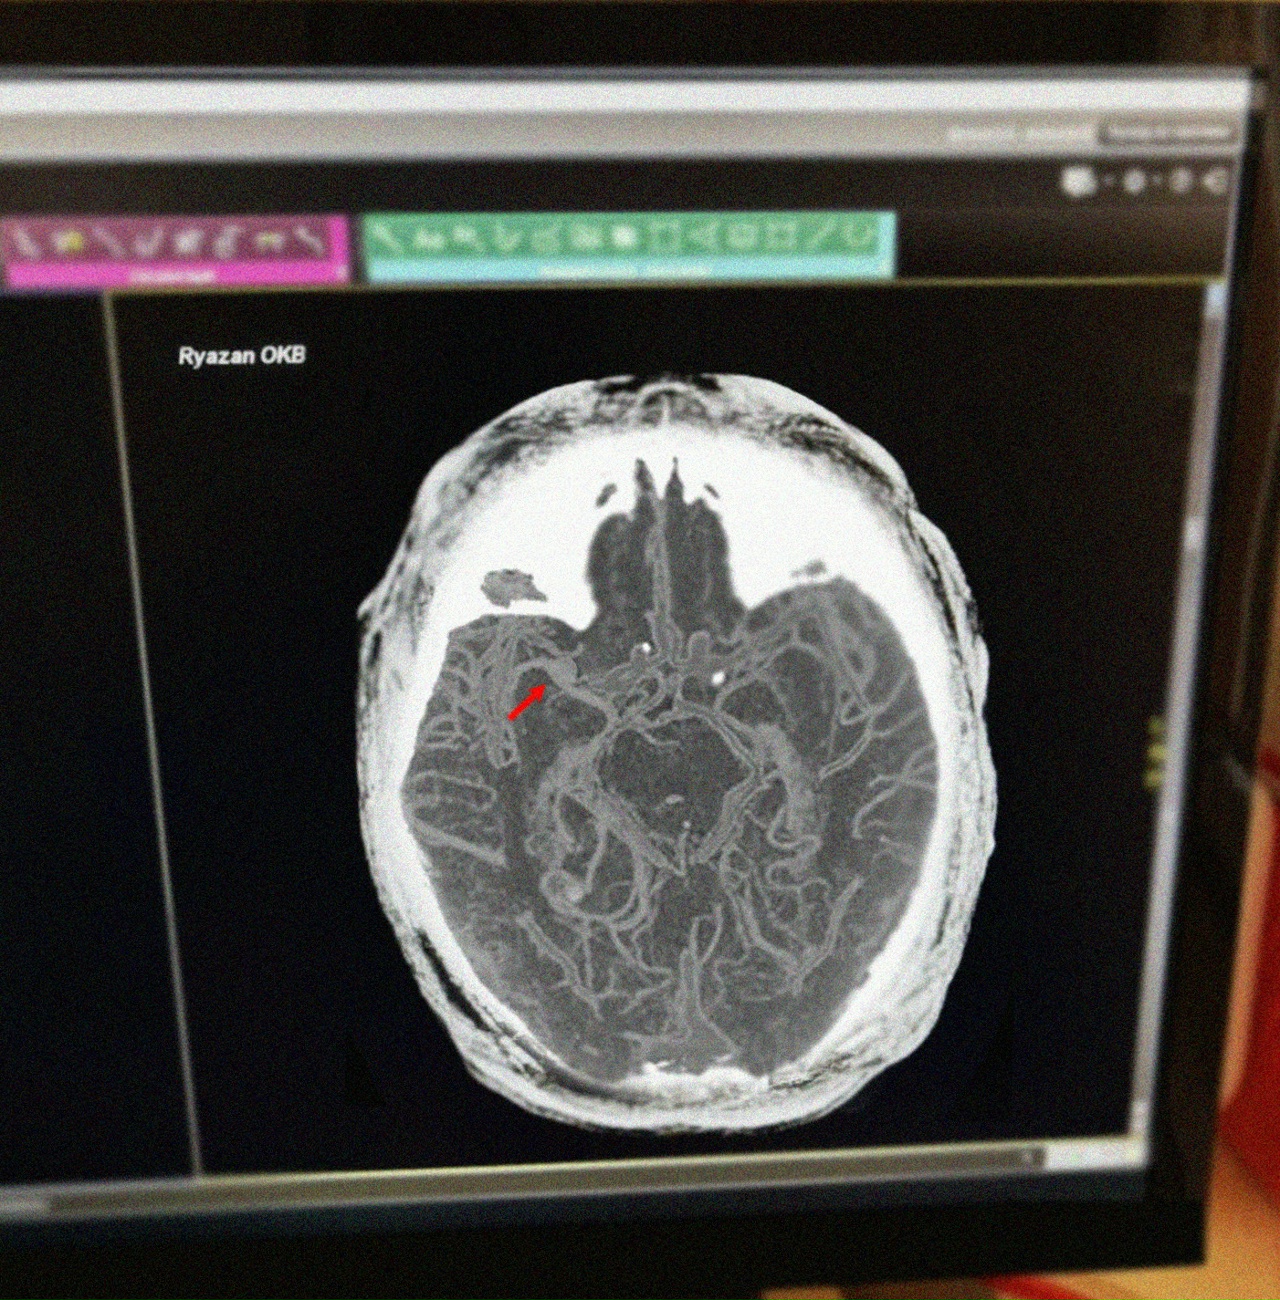

Прибывшие медики оперативно диагностировали инсульт и срочно доставили пострадавшего в отделение неврологии Рязанской областной клинической больницы. Проведённое обследование подтвердило наличие острого ишемического инсульта головного мозга.

Пациенту назначили срочную процедуру тромболизиса, позволяющую растворять тромб и восстанавливать кровообращение. Особенную значимость имела скорость реагирования медиков: от первых признаков заболевания до поступления в стационар прошло меньше двух часов, что позволило избежать тяжёлых осложнений.

Процедуру провёл заведующий отделением ОНМК кандидат медицинских наук, врач высшей категории Олег Сорокин. Как объяснил доктор, тромболизис – единственный эффективный способ быстрого восстановления кровотока при остром тромбозе сосудов мозга. Но такая процедура должна проводиться исключительно квалифицированными специалистами в условиях стационара и только после подтверждения диагноза и исключения противопоказаний.